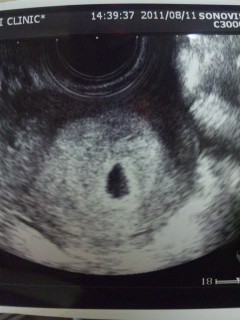

不妊治療(1年2ヵ月)を経ての妊娠です♪

本当は5w2dに検診予定だったのですが

4w6dに鼻・喉風邪をひいてしまい

心配になって受診♪

確認とれないかと思っていたら

胎嚢確認(7.9mm)出来ました

次は6w3dにクリニックです。

心拍確認とれますようにっ